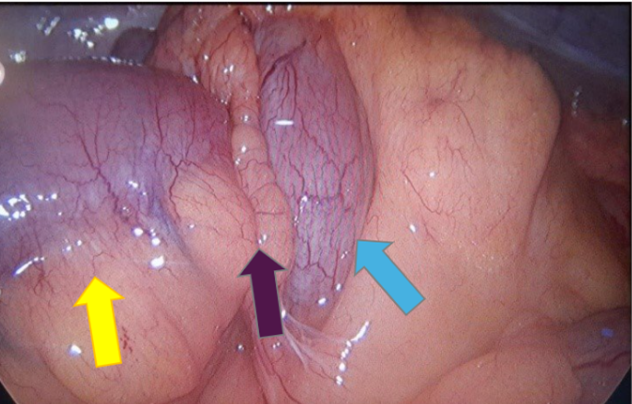

Male patient, 62 years old, overweight, hypertensive and regularly using antihypertensive medication, admitted to the digestive system surgery service at Hospital da Cidade-Salvador- Bahia- Brazil, with clinical symptoms of abdominal pain in the hypogastrium, radiating to the right iliac fossa. Report of abrupt onset, with strong intensity and no improvement after analgesia. Pacient reports passing gas and feces. On physical examination, the abdomen was globular due to a fatty panniculus, without abdominal distension, tympanic, painless on superficial and deep palpation. Surgical history: conventional appendectomy, 10 years ago. Computed tomography of the total abdomen showed a point of mechanical obstruction at the level of the distal ileum and cecum, with classic radiological signs of intestinal intussusception: pseudokidney sign (Figure 1) and target sign (Figure 2). In a multidisciplinary discussion with the radiolo team specialized in the digestive system, radiological characteristics of benign lipomatous neoplasia were highlighted: Lesion measuring 4.8 x 3.0 cm, associated with well-defined margins, rounded and with a fat density similar to that of mescolon, without prominent peri-colonic lymph node (Figure 3). The patient's clinical condition worsened due to abdominal distension and post-food vomiting, undergoing surgical treatment with resection of the distal ileum and cecum and primary anastomosis. No need for wide colectomy or retroperitoneal lymphadenectomy. The patient was discharged from hospital on the 5th postoperative day without abdominal pain, with a bland oral diet and normal intestinal rhythm. Pathological anatomy showed a benign lipomatous lesion measuring (4.5 x1.5 cm) in the ileum.

Figure 4. Intraoperative photo showing intussuscepted segment (yellow arrow: distal ileum; blue arrow: cecum; purple arrow: site of intussusception).